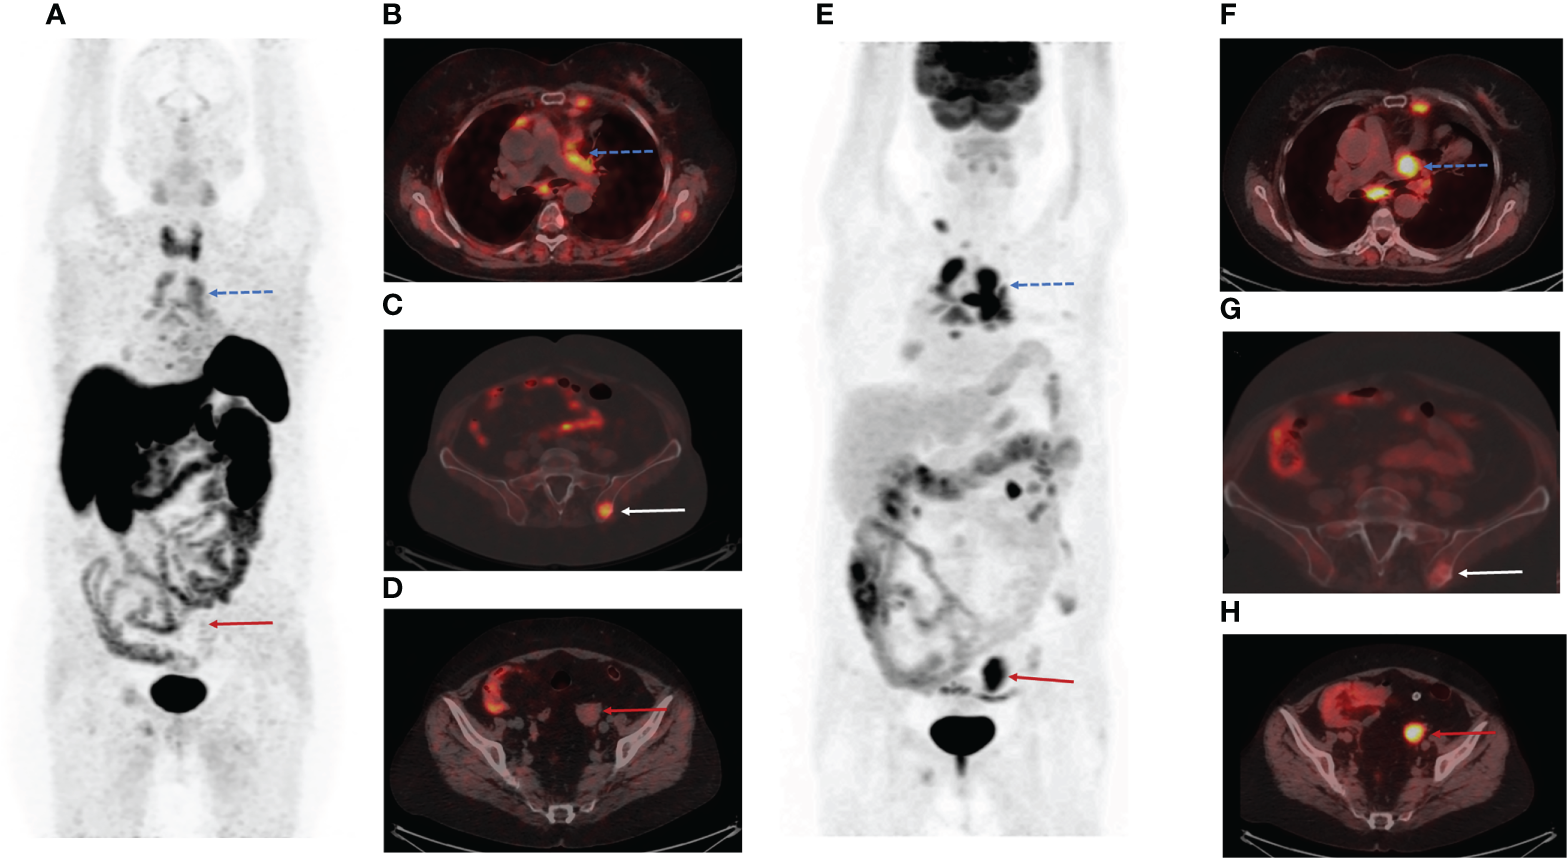

The patient underwent PET/CT with [68Ga]-DOTA-TATE. [68Ga]-DOTA-TATE was synthesized in compliance with the European Pharmacopoeia (Gallium[68Ga] Edotreotide injection 01/2013: 2482 corrected 8.6). PET/CT scan was performed in 60 minutes after intravenous administration of 150 MBq of radiopharmaceutical. PET/CT scan showed multiple mediastinal lymphatic nodes, and widespread bone metastases with significant uptake of [68Ga]-DOTA-TATE (Figures 1A–C). Moreover, PET/CT revealed [68Ga]-DOTA-TATE negative solid mass in the left ovary (size 34x30x47 mm) (Figure 1D), peritoneal implants, and enlarged right cervical lymphatic node.

Figure 1

Positron emission tomography/computed tomography (PET/CT) images with Gallium-68 [68Ga]-labeled dodecanetetraacetic acid-tyrosine-3-octreotate ([68Ga]-DOTA-TATE) and Fluor-18 [18F]-fluorodeoxyglucose ([18F]-FDG). (A) The maximum intensity projection (MIP) images summarize the physiological and pathological distribution of [68Ga]-DOTA-TATE in the body. (B) PET/CT scan showed multiple mediastinal lymphatic nodes (blue dotted arrow) and widespread bone metastases with significant uptake of [68Ga]-DOTA-TATE. (C) [68Ga]-DOTA-TATE-positive bone metastasis in the left iliac wing (white arrow). (D) [68Ga]-DOTA-TATE-negative solid mass in the left ovary (red arrow). (E) The MIP images summarize the physiological and pathological distribution of [18F]-FDG in the body. (F) Multiple [68Ga]-DOTA-TATE-positive metastases in mediastinal lymphatic nodes (blue dotted arrow). (G) The axial PET/CT image demonstrated low [18F]-FDG uptake in the bone metastasis in the left iliac wing (white arrow). (H) The axial slice of [18F]-FDG PET/CT showed high [18F]-FDG uptake in the solid mass in the left ovary (red arrow).

We assumed that the patient had poor differentiated neuroendocrine tumor in the left ovary. The patient was referred for PET/CT with Fluor-18 [18F]-fluorodeoxyglucose ([18F]-FDG), which was performed three days after the first PET/CT. PET/CT [18F]-FDG showed high uptake of the radiopharmaceutical in a solid mass of the left ovary (SUV max= 6,49) (Figures 1E, H), peritoneal implants (SUV max= 1,54), right cervical lymphatic node (SUV max= 3,91), and several mediastinal lymphatic nodes (SUV max= 3,67) (Figures 1E, F). However, we observed accumulation of [18F]-FDG in only a few bone metastases (Figure 1G).